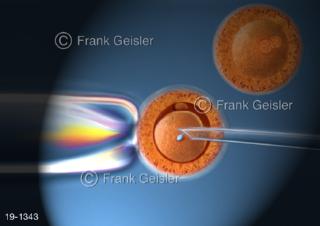

Bilder zu Medical Art und Anatomie-Art, visuelle Darstellung medizinischer Inhalte künstlerisch umgesetzt, medizinisches Fachwissen als künstlerische Gestaltung für die Ausbildung, zur Patientenaufklärung und zur wissenschaftlichen Kommunikation, als künstlerische Dekoration in Gesundheitseinrichtungen und Arztpraxen

© MediDesign Frank Geisler